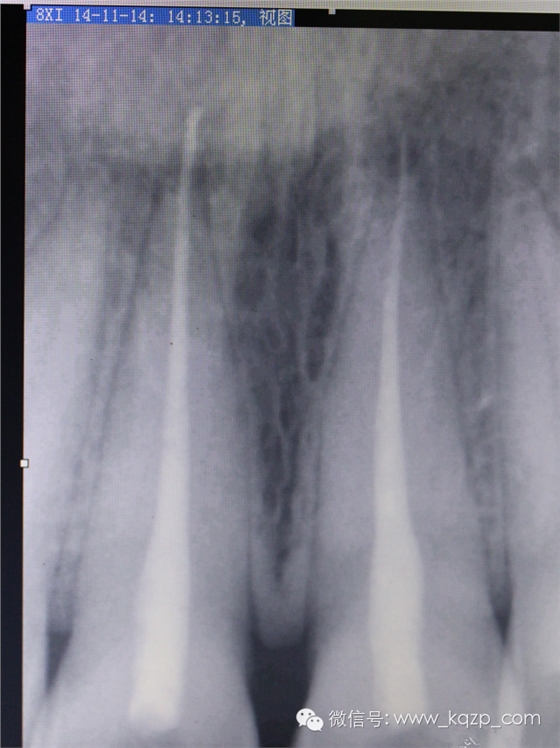

患者在外院治療結(jié)束3個月,感覺咬合無力就診。

拍片見35根管治療后超充。

約診拆根充,看能否把超充取出,如不能取出則考慮拔牙或者根尖手術(shù)。

上段牙膠取出無殊,常規(guī)方法。待近根尖時,先用丁克除棉捻軟化片刻不超過5分鐘,拿出棉捻,用拔髓針輕柔緩緩旋入,此時如果有稍緊的感覺即停,試著慢慢拉出,多數(shù)會把根尖部的牙膠完整帶出。

哈哈,成功了。

拍片,

順手把工作長度也確定下。